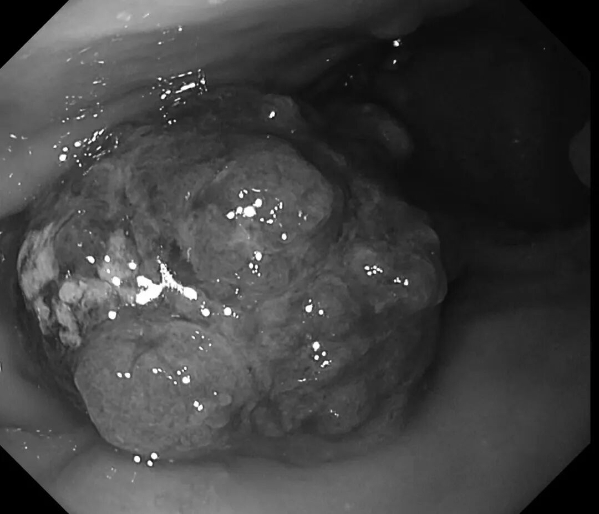

患者李先生(化名),60多岁,平日不抽烟不喝酒,无任何消化道症状,但有家族史,在子女的带领下来做胃肠镜精查。前两年刚做过胃肠镜,未发现异常。在新镜界精查中,发现胃角处有一黏膜与正常略微不同,经NBI+放大内镜放大观查,考虑胃早癌,活检证实为高级别上皮内瘤变。恰逢麻兴华教授(新镜界日方特聘专家)来院坐诊,于是由麻教授带领内镜团队行内镜下黏膜剥离术(ESD),术后患者痊愈。

因为是早期胃癌,在内镜下行黏膜剥离术(ESD),就能够治愈,无需外科手术及放化疗。这是不幸中的万幸,患者今后只需定期胃镜复查即可。